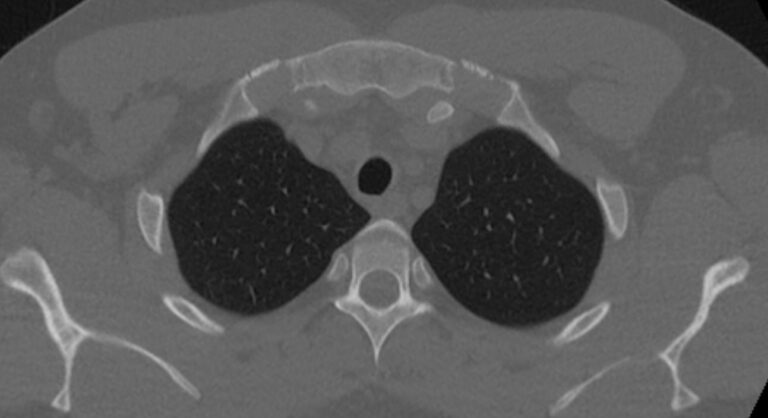

При проведении мультиспиральной компьютерной томографии на снимках и трехмерных изображениях хорошо видны костные структуры грудины, передней поверхности ребер, грудино-ключичных и грудино-реберных сочленений. Также можно увидеть строение и патологические процессы в органах средостения: трахеи, пищевода, лимфатических узлов средостения, вилочковой железы, загрудинно расположенной щитовидной железы, грудной аорты, сердца и перикарда, жировой клетчатки средостения.

С помощью мультиспиральной КТ грудины можно диагностировать: